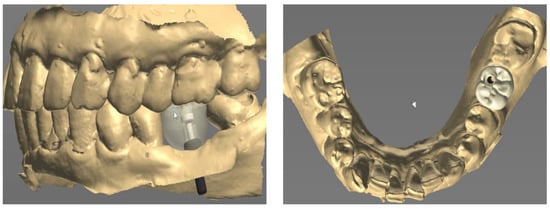

Next, a healing cap was connected to the multi-abutment (Figure 3A). The healing cap served as a normal healing abutment and an impression coping, intended for impression taking through recognition points on the occlusal surface, was also placed. The final impressions were taken using an addition-type silicone impression material (Aquasil LV and XLV; Dentsply Sirona, Milford, DE, USA). In a dental laboratory, the master model obtained from the impression was model-scanned, and the scan data was sent to a computer-aided design (CAD) software program (Trios II; 3Shape, Copenhagen, Denmark) (Figure 3B).

The final prosthesis was designed on a CAD software program through using the scanned information (Figure 4). The prefabricated link with appropriate height and diameter was selected considering the positional relationship between the implant and adjacent teeth and opposing teeth.

Figure 3. (A) Healing cap connection, (B) Model scan data.

Figure 4. Prosthetic design of implant prosthesis on CAD software program.